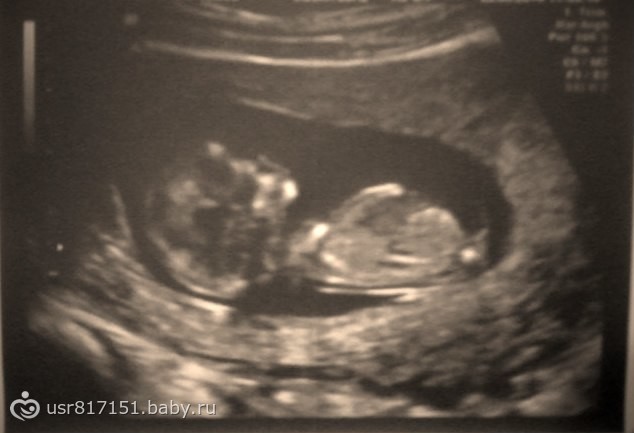

Смотрю на узи и не понимаю что вижу (((

это попа с ножками. это фото с такого ракурса, какбудто бы вы сели бына стул, и вас бы снизу сфоткали)

у вас действительно как будто богорок лежит внизу

По наклону полового бугорка ;-) У девочек и мальчиков до 16 -17 неделе там отросток , у девочек он смотрит вниз или паралельно телу и потом уходит внутрь и превразается в клитор , у мальчиков резко ввенрх на 90 градусов (как стоит писька) естественно никуда уже не уходит и превращается в пенис)) Вот наш мальчик (торчком) на 12ой неделе! Ему уже 2 года! Поищите фото девочек иполвой бугорок в инете